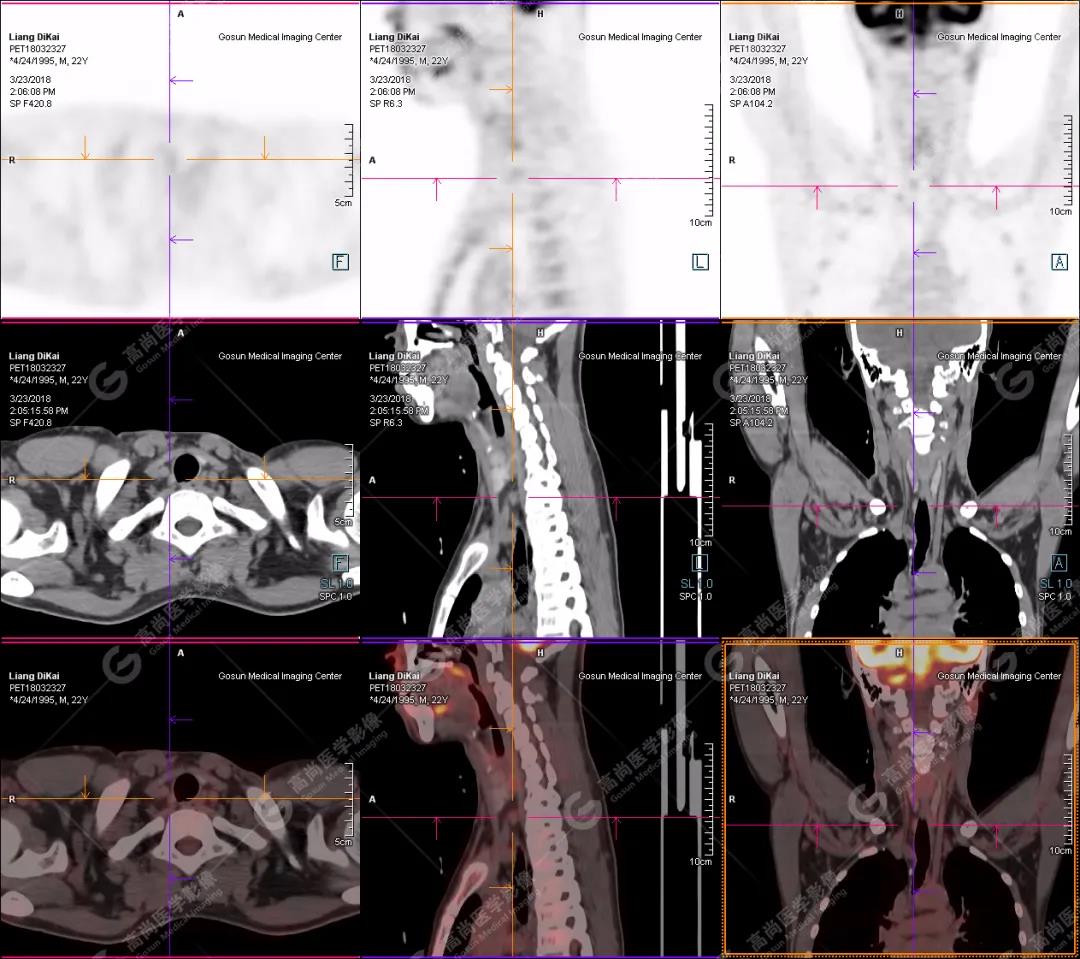

【廣東高尚醫(yī)學(xué)影像病例】PET/CT在副腫瘤綜合征尋找原發(fā)灶應(yīng)用

男性,23歲,反復(fù)血鈣升高1年;左側(cè)臀部、右肘部腫物進(jìn)行性生長2年。既往2017年尿毒癥腎移植術(shù)后;鈣磷代謝異常。否認(rèn)結(jié)核、乙肝等其它手術(shù)史。

本中心PET/CT提示

1.右肘關(guān)節(jié)周圍、骶尾部皮下、雙側(cè)臀部、盆腔左側(cè)壁及左側(cè)大腿根部肌肉、肌間隙多發(fā)結(jié)節(jié)狀、片塊狀及不規(guī)則巨塊狀高密度鈣化灶,伴代謝不均勻輕度增高,考慮為鈣質(zhì)沉著癥;

2.甲狀腺雙葉后方多發(fā)(右2個,左1個)小結(jié)節(jié)狀軟組織影,部分代謝輕度增高,多考慮為甲狀旁腺腺瘤。

患者行甲狀腺雙葉后方結(jié)節(jié)切除,術(shù)后病理甲狀旁腺腺瘤;病灶切除后,全身多發(fā)腫塊逐漸消失。